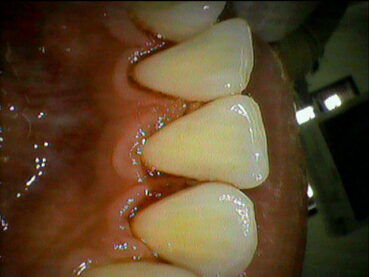

歯周病とは、歯茎(歯肉)に炎症が起こり、進行すると歯を支えている骨が溶けてしまう病気です。

初期の段階では「歯茎が赤く腫れる」「歯みがきで出血する」といった軽い症状しかないため、気づかないまま進行してしまうことが多くあります。

歯周病の原因は、歯と歯茎の間にたまる「プラーク(歯垢)」の中に潜む細菌です。これが歯茎に炎症を起こし、やがて骨まで溶かしてしまいます。